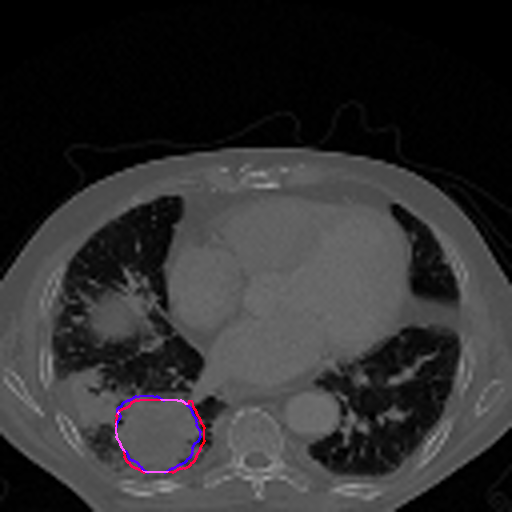

Figure 5 shows a comparison between predictions by the MultiResUNet model and Deeply supervised MultiResUNet model. It can be seen that the latter can delineate the tumor edges more accurately than the former. The ground truth (shown in red) and the prediction (shown in blue) have a more consistent alignment with each other in Deeply Supervised MultiResUNet’s prediction.